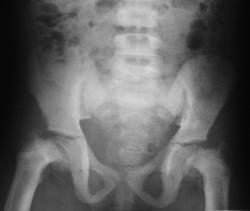

Подскажите, учитывая все данные (клинико-рентгенологические) как бы звучало ваше заключение? Слева, это патологический перелом или такая патологическая деформация головки и шейки бедренной кости?

Патологический процесс с обеих сторон в ростковых зонах, в результате чего нарушена энхондральная оссификация шеек бедер, идет их резорбция и головки смещаются книзу. Причиной этого, в данном случае, является почечная недостаточность. А в заключении, наверное, можно написать - варусная деформация бедер на фоне почечной остеодистрофии.

Спасибо DR.RAD и Ola-la, что не оставили без внимания, за ваши ценные комментарии. А девочка оказалась не такой уж и простой. На сегодняшний день ее диагноз звучит так: Хр. почечная недостаточность 4 стадия. ВАРМС: агенезия правой почки, мегауретер слева, кистозная дисплазия левой почки. Вторичный хронический пиелонефрит. Нефрогенная анемия. Нефрогенная остеопатия. Деформация костей нижних конечностей, плоско-вальгусные стопы.

Сегодня сделали рентген в прямой проекции бедренных костей, костей голени (к сожалению не было возможности сфотографировать) : соотношения в суставах не нарушены. Отмечается варусная деформация нижней третей бедренных костей, и костей нижней трети правой голени. Умеренный остеопроз.